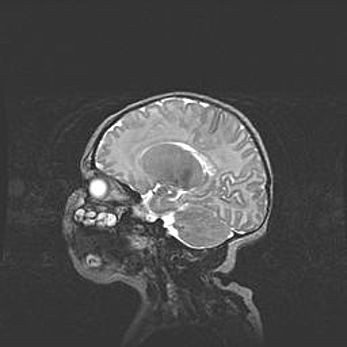

Сообщающаяся гидроцефалия. Кистозная энцефаломаляция головного мозга.

Возраст: 3 месяца 4 дня

Вес: 3100 г

Пол: женский

Окружность головы: 34 см

Срок гестации: 31 неделя

Кистозная энцефаломаляция головного мозга - одна из форм поражения головного мозга в детском возрасте. Характеризуется возникновением множественных и распространённых кист в коре, белом веществе и подкорковых образованиях головного мозга у плодов, новорождённых и детей раннего возраста. Развитие кистозной энцефаломаляции связано с внутриутробной асфиксией и гипотонией, родовой травмой, тромбозом синусов, пороками развития сосудов, инфекциями, сепсисом и другими причинами. Наиболее значимые инфекционные агенты: вирусы простого герпеса, цитомегалии, краснухи, токсоплазмы, энтеробактерии, золотистый стафилококк и другие.